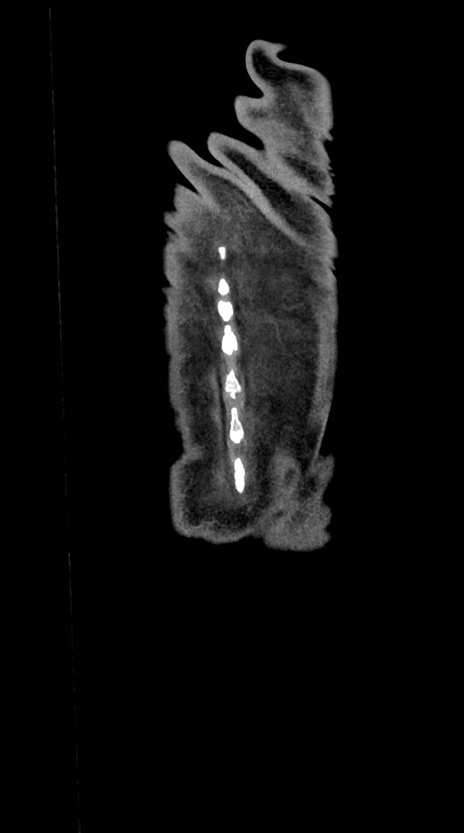

【症例】60歳代男性

【主訴】嘔吐

【現病歴】胃癌にて胃全摘後。食思不振が悪化し、夜中に嘔吐することがある。

【既往歴】胃癌、胃全摘、脾摘、胆摘後

【データ】WBC 5900、CRP 10.56